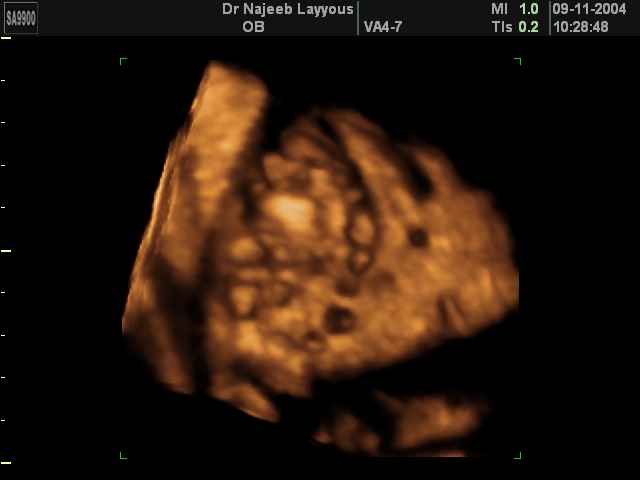

صور طبية للحمل بجهاز الالتراساوند | الدكتور نجيب ليوس